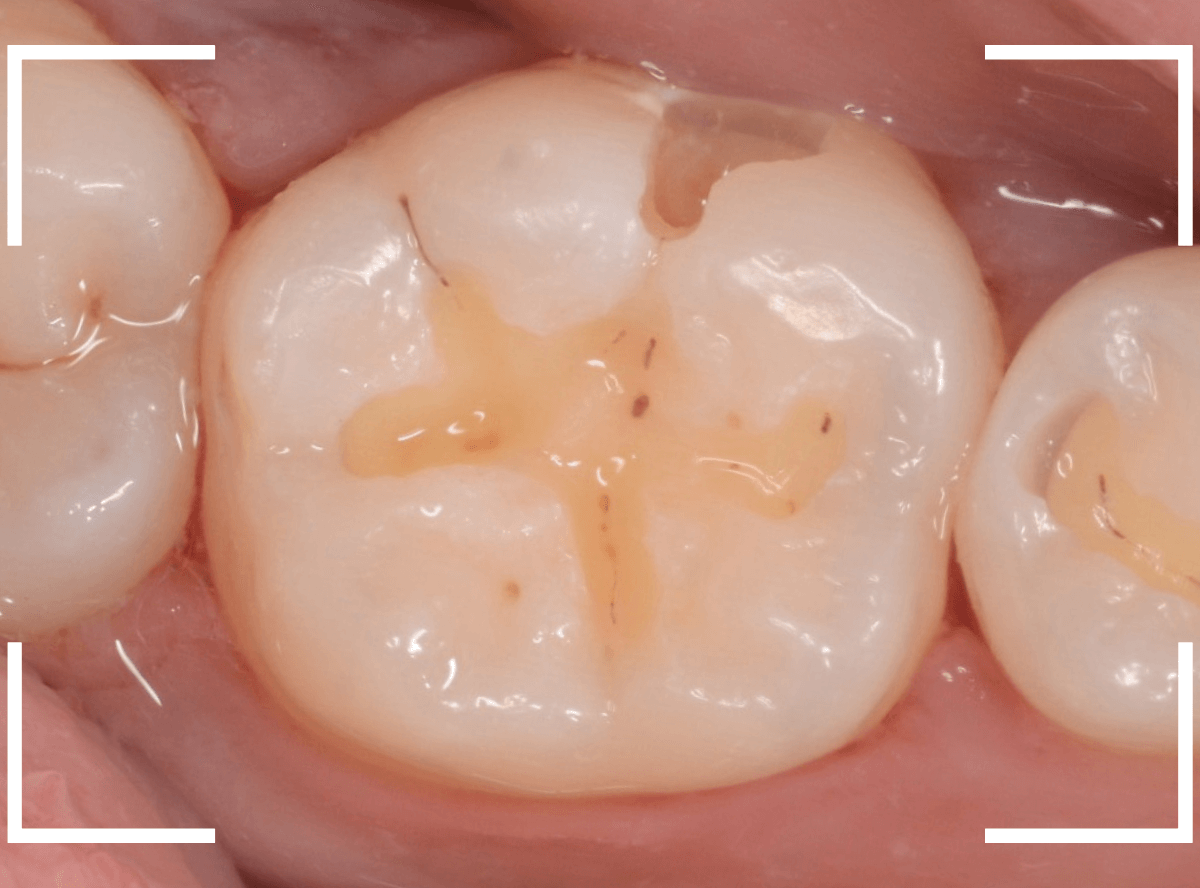

Case.8 大きな虫歯なのに、レントゲンではっきり写らない

こちらも定期検診希望で来院された患者さんです。

お口の中を拝見すると、明らかに虫歯がありました。

3本虫歯になっており、特に中央の小臼歯はかなり大きな虫歯になっているのが予想されます。

治療前にレントゲン写真で虫歯の大きさを確認するつもりが・・・あまりはっきり写ってきません。

患者さんに状況を説明して、歯を少しずつ削りながら虫歯を確認する事になりました。

まず、一番大きな虫歯と思われる部分を小さく削って確認します。

予想通り、虫歯が見えてきました。

隣りの奥歯と一緒に虫歯の治療を進めます。

色が染まっているところがまだ虫歯が残っている部分です。

2本とも、虫歯を全て取り切りました。

特に手前の歯はかなり広めの虫歯になっていました。

最終的に、手前の虫歯の除去も終わったところです。

手前の歯の虫歯は中央の歯まで達していました。

このように明らかに大きな虫歯があると診断されるような状況でも、レントゲン写真でうまく診断できない場合もあります。